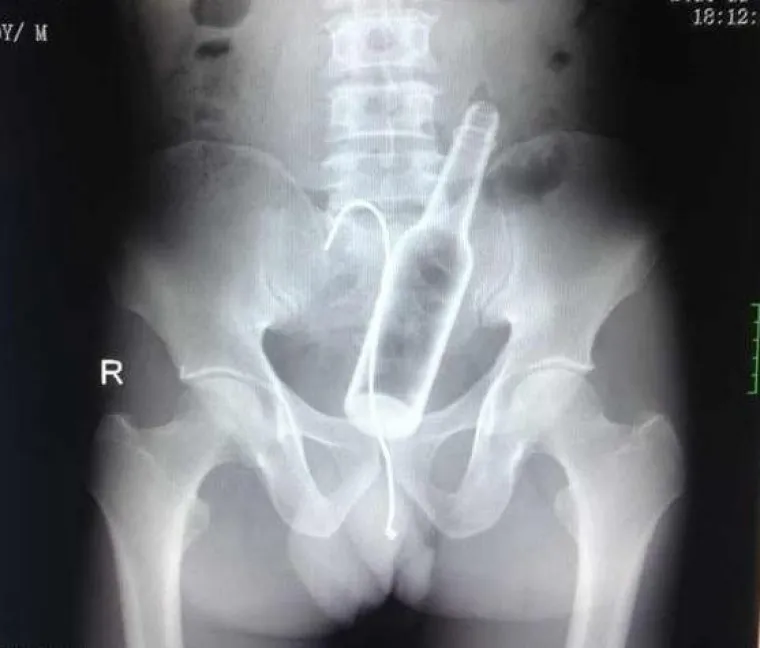

Doktori podijelili povjerljive slike pacijenata koji su u sebe ugurali sve i svašta

Boca